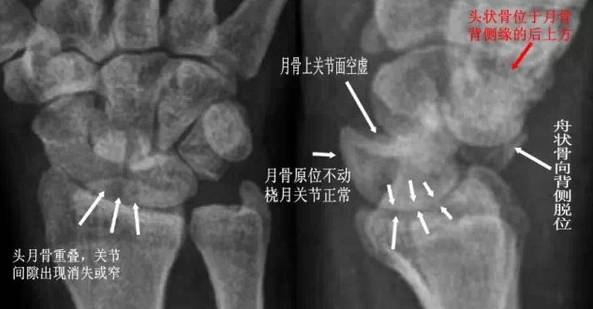

(1)月骨脱位:正位片示月骨由四边形变成三角形或橘瓣状,并向尺侧移位。侧位月骨前移、旋转,窝状关节前空虚。

月骨脱位影像特点

(3)月骨周围脱位:表现为腕关节缩短,头骨与桡骨距离变近,头骨、钩骨与月骨部分重叠,月骨形态及位置基本正常。

月骨周围脱位影像特点